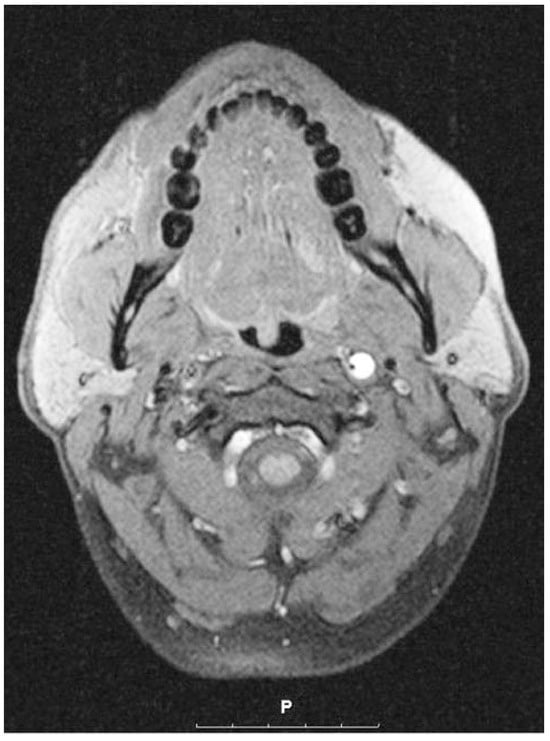

Carotid Artery Dissection and Sports

by Marcel Arnold, Urs Fischer and Krassen Nedeltchev

Carotid artery dissection (CAD) is a potentially lifethreatening disease and mainly affects young and middle- aged people. In recent years dissections have been diagnosed more frequently, probably because new imaging techniques allow more reliable diagnosis. The cause of so-called spontaneous CAD is largely [...] Read more.

Carotid artery dissection (CAD) is a potentially lifethreatening disease and mainly affects young and middle- aged people. In recent years dissections have been diagnosed more frequently, probably because new imaging techniques allow more reliable diagnosis. The cause of so-called spontaneous CAD is largely unexplained. It most likely involves an underlying abnormality of the vessel wall and triggering factors such as infection, minor trauma or sporting activities. Various sporting activities have been reported in association with CAD. Nevertheless, the causal relationship between sporting activities and CAD often remains doubtful. Traumatic CAD mainly complicates severe blunt head or neck traumas, which are often due to motor vehicle or sport accidents.

The clinical presentations of CAD are highly variable. Headache, neck and facial pain, pulsatile tinnitus, Horner’s syndrome, cranial nerve palsies, stroke, TIA, retinal infarction, or transient monocular blindness, may be present in isolation or in various combinations. Ischaemic symptoms are often preceded by local symptoms or signs. The knowledge and recognition of these symptoms and the often subtle signs are the keys to an early diagnosis and antithrombotic treatment of ICAD before severe ischaemic complications occur. The longterm prognosis of CAD is favourable in the majority of patients. Clinical functional outcome mainly depends on the initial stroke severity. Symptomatic recurrent dissections and recurrent strokes are rare. Full article

Show Figures

Figure 1